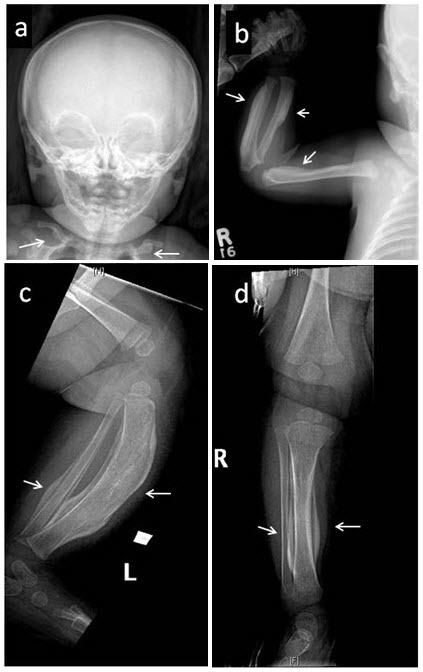

卡菲病,也叫婴儿骨皮质增生症,是一种常见于婴儿的骨病。卡菲病的主要特征是新生骨过度产生。骨骼异常主要影响颚骨、肩胛骨、锁骨、手臂和腿的长骨骨干。病变骨的宽度可以增加至原来的两到三倍,这可以通过x射线成像看到。在某些情况下,彼此相邻的两个骨病变,如两个相邻肋骨或前臂相邻的长骨(桡、尺骨)或小腿相邻长骨(胫、腓骨)融合在一起。卡菲疾病的患儿也可有关节和肌肉等软组织疼痛、红肿。患病的婴幼儿还可能发热、烦躁。 卡菲病的症状和体征通常在患儿5个月前出现。在极少数情况下,骨骼畸形在出生前几个星期内发生,可以通过超声影像检查发现。产前致死性皮质醇增多是一种更为严重的疾病,可导致新生儿在出生前或出生后不久死亡,有时也被称为产前致死性卡菲病,但通常被看作一个独立的疾病。 卡菲病相关的肿胀和疼痛症状通常在几个月内缓解,原因需要借助致病基因鉴定基因解码进行明确。通过正常的骨重建过程,过量的骨通常在患者2岁之前溶解吸收并被新生骨取代, x射线图像上检测不到病症。然而,如果是关节处两个相邻的骨发生融合,则很可能不会自然溶解吸收,因此会导致相关症状。例如,肋骨融合可导致脊柱侧凸、或胸廓活动受限,导致呼吸问题。 大多数卡菲病患者度过幼儿期后没有进一步的症状,偶见骨质增生于数年后再次反复。此外,一些曾在婴儿期患卡菲病的人成年后伴有其他骨骼系统或结缔组织病变,骨骼与结缔组织维持身体强度和柔韧性,受影响的患者会出现关节松弛,皮肤弹性增加或疝。